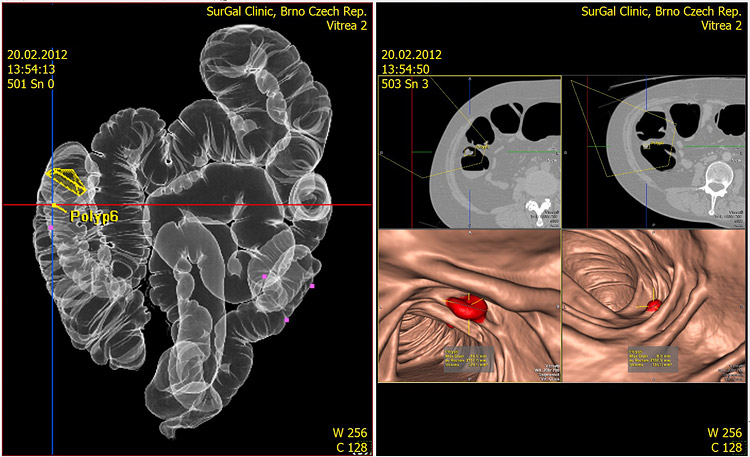

V SurGal Clinic provádíme neinvazivní vyšetření tlustého střeva na nejmodernějším 64řadém CT stroji Toshiba Aquilion vybaveném speciální rekonstrukční pracovní stanicí Vitrea.

CT virtuální kolonoskopieumožňuje virtuální pohled a pohyb luminem tlustého střeva v celé jeho délce po dostatečné rozepnutí tleustého střeva vzduchem nebo oxidem uhličitým.

Pro polypy velikosti 1 cm a více dosahuje senzitivita a specificita 90-100 %, pro polypy velikosti 5-9 mm 60-75 % a pro polypy velikosti menší než 5 mm je senzitivita a specificita pouze asi 25 %. Hlavní snahou tohoto vyšetření je tedy zachytit polypy větší než 5 mm, které již pro pacienta mohou do budoucnosti znamenat určité riziko a pacienta s tímto nálezem dispenzarizovat. Při porovnání „klasické“ endoskopické kolonoskopie a virtuální kolonoskopie má právě virtuální kolonoskopie celou řadu nepopiratelných výhod: